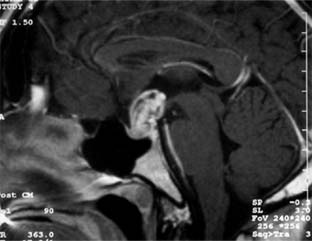

Craniopharyngiomas are an uncommon group of tumors arising from epithelial remnants of Rathke's pouch (80% of the population normally have such remnants) and characteristically become symptomatic between the ages of 10 and 25 years but occasionally not until the 60s and 70s. They are usually suprasellar (Figure 14-27), occasionally intrasellar. The signs and symptoms vary tremendously with the age of the patient and the exact location of the tumor as well as its rate of growth. When a suprasellar tumor occurs, asymmetric chiasmatic or tract field defects are prominent. Papilledema is more common than in pituitary tumors. Optic nerve hypoplasia can be seen in those tumors presenting in infancy. Pituitary deficiency may result, and involvement of the hypothalamus may cause stunted growth. Calcification of parts of the tumor contributes to a characteristic radiologic appearance, especially in children.

Figure 14-27

Figure 14-27: Sagittal MRI showing contrast enhanced suprasellar craniopharyngioma.